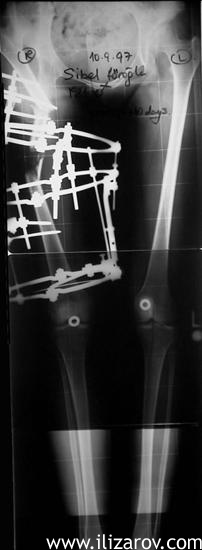

4. Hastanın tedavi sırasında AP ortoröntgenografisi